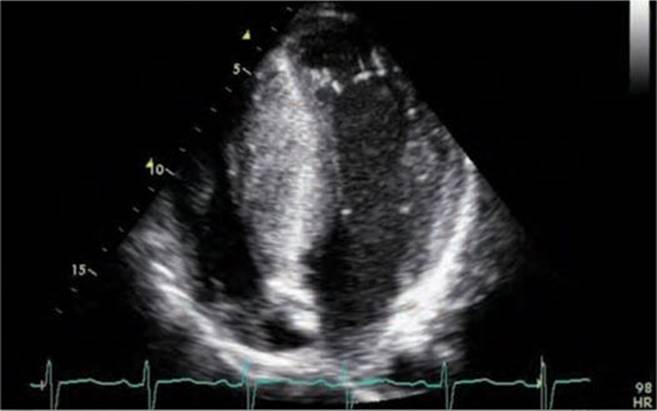

Physical examination revealed a systolic murmur that worsens with rapidly standing, squatting, and standing again. A 12-lead ECG reveals prominent QRS voltage in the precordial leads with deep T-wave inversions (Figure 53-1). An echocardiogram was obtained demonstrating a nearly 5 cm ventricular septum and mitral regurgitation secondary to systolic anterior motion of the mitral valve (SAM) (Figures 53-2 to 53-5). A resting left ventricular outflow tract (LVOT) gradient of 45 mm Hg was recorded with a provocable gradient of >80 mm Hg (Figure 53-6).

FIGURE 53-2 Echocardiogram demonstrating asymmetric hypertrophy with nearly a 5-cm septum.